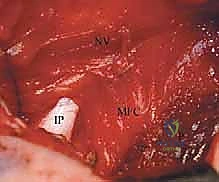

بحرص شديد لتجنب الأوعية الدموية والأعصاب الحيوية (مثل الحزمة الوعائية العصبية الفخذية والعصب السدادي)، يتم إبعاد العضلات المقربة (Adductor muscles). في بعض الحالات، يتم تحرير (قطع جزئي) لوتر العضلة المقربة الطويلة (Adductor Longus) لتخفيف الشد على المفصل.

الخطوة 4: تحرير وتر العضلة الحرقفية القطنية (Psoas Tendon Release)

هذا هو أحد أهم أجزاء العملية. وتر العضلة الحرقفية القطنية يكون مشدوداً جداً في حالات DDH ويشكل حاجزاً يمنع رأس الفخذ من النزول إلى مكانه. يقوم الدكتور هطيف بعزل هذا الوتر وقطعه بدقة، مما يزيل الضغط الفوري عن المفصل.

الخطوة 5: فتح الكبسولة المفصلية (Capsulotomy)

بمجرد إزاحة الوتر، تظهر الكبسولة المفصلية بوضوح. يتم إجراء شق دقيق في الكبسولة (غالباً على شكل حرف T أو H) للوصول إلى داخل المفصل.

الخطوة 6: تنظيف التجويف الحقي (Clearing the Acetabulum)

الآن، يرى الجراح داخل المفصل. هنا تبرز الخبرة في إزالة العوائق الداخلية:

* يتم استئصال الرباط المدور (Ligamentum Teres) المتضخم الذي يشغل حيزاً كبيراً.

* يتم إزالة الأنسجة الليفية والدهنية المعروفة باسم البولفينار (Pulvinar).

* يتم شق الرباط الحقي المستعرض (Transverse Acetabular Ligament) إذا كان ضيقاً ويمنع دخول رأس الفخذ.

الخطوة 7: الرد الفعلي للمفصل (Reduction)

بعد تنظيف التجويف تماماً، يقوم الدكتور هطيف بتوجيه رأس عظم الفخذ بلطف شديد ليدخل ويستقر بعمق داخل التجويف الحقي. يجب أن يكون الرد مستقراً وسلساً دون الحاجة إلى قوة مفرطة. يتم فحص استقرار المفصل في وضعيات مختلفة للتأكد من عدم خروجه مرة أخرى.